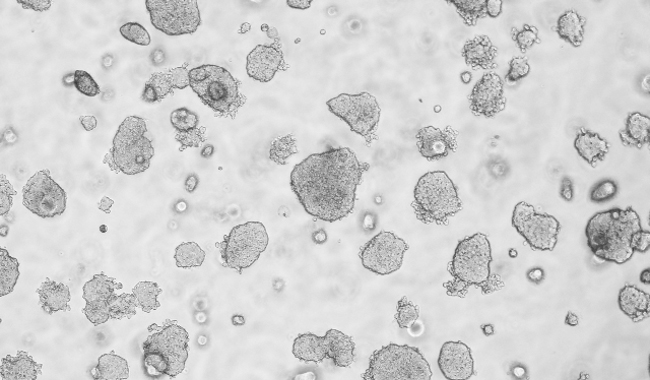

平板克隆形成圖像分析

平板克隆試驗是一種常用的測量細胞生長能力的技術,從開始已知的細胞群體監(jiān)測菌落的形成。菌落的形成需要密集的分裂的原始細胞,所以在整個實驗的細胞或菌落的數量的量化是細胞的生長潛力的指標。因此,集落形成試驗已成為一種廣泛用于癌癥研究的方法來研究藥物和電離輻射療法對癌細胞增殖的影響。